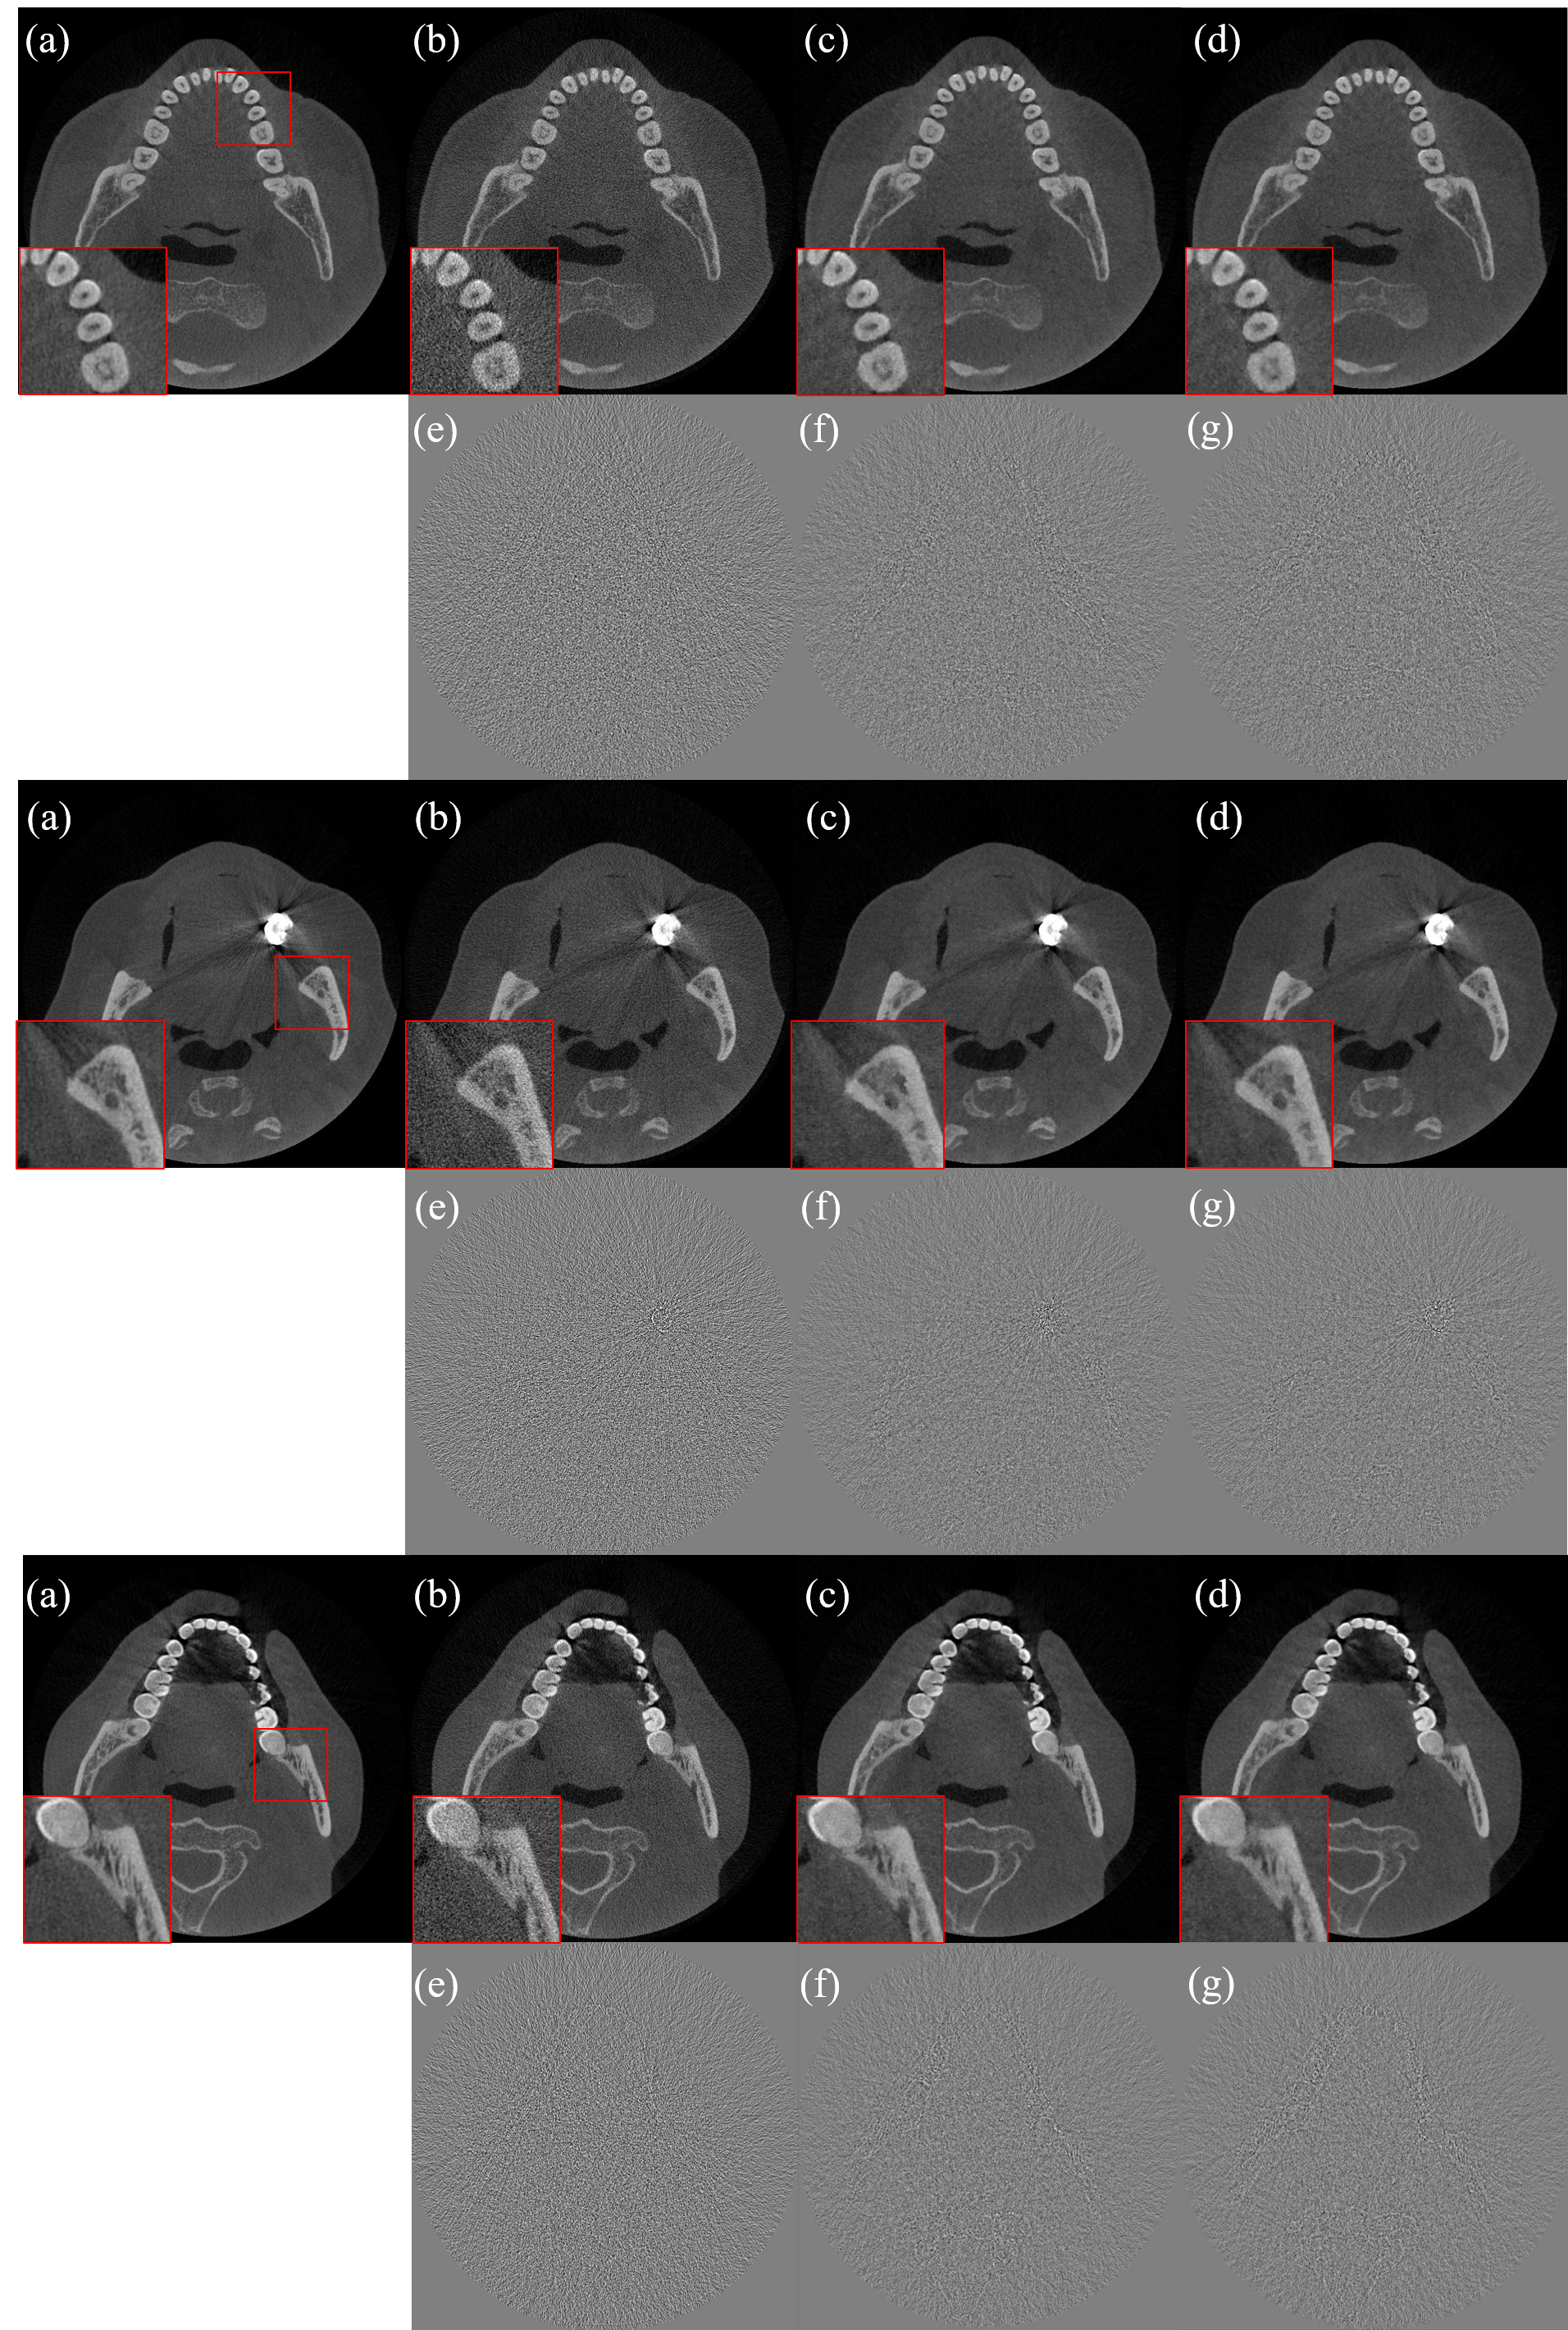

In Fig.3, FBP reconstruction of NDCT with Hanning filter, LDCT FBP reconstruction with Hanning filter, NLM-WLS iterative reconstruction, and MBDL network reconstruction were displayed for visual comparison. We applied a 5-order Hanning window filtration in FBP reconstructions for noise reduction in this comparison. Details denoted by red arrow were zoomed-in and displayed in the lower right corner. Similar with full-simulation cases, both iterative reconstruction and MBDL network reconstruction suppressed the noise and restored rich structures of teeth. The two algorithms achieved similar visual results.